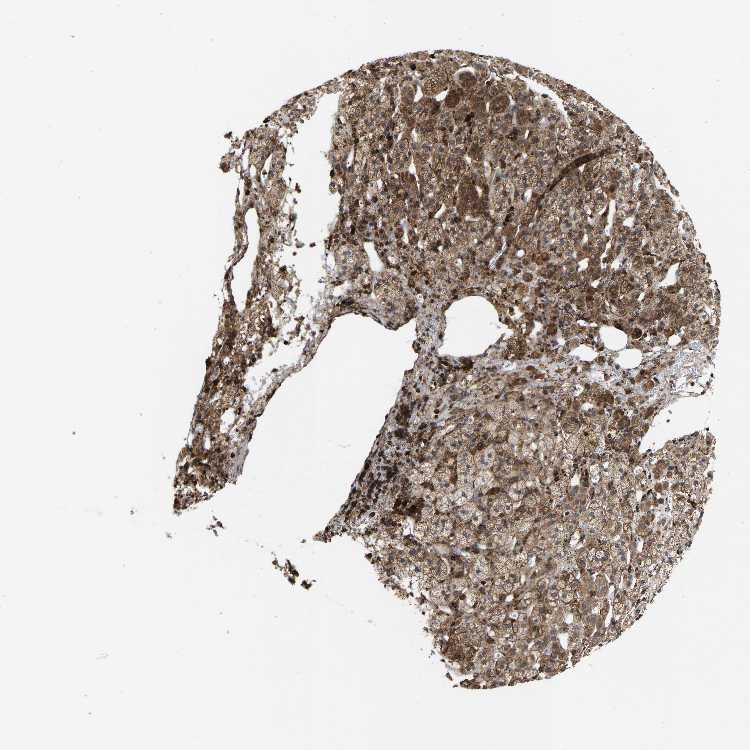

ADRENAL GLAND - Antibody stainingi

Antibody staining in the annotated cell types in the current human tissue is reported as not detected, low, medium, or high, based on conventional immunohistochemistry profiling in selected tissues. This score is based on the combination of the staining intensity and fraction of stained cells.

Each image is clickable and will lead to virtual microscopy that enables deeper exploration of all samples and also displays staining intensity scores, fraction scores and subcellular localization as well as patient and tissue information for each sample.

Antibody HPA020963Antibody HPA021018

Glandular cells MediumNot detected